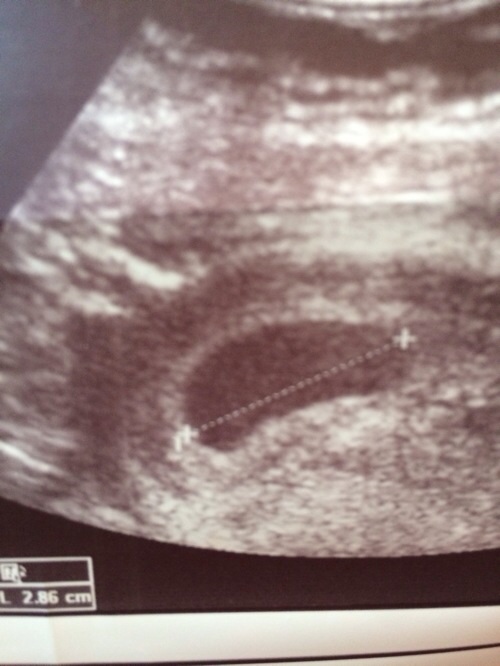

Findet ihr auch, das die FH recht deformiert ist? Der US wurde über die bauchdecke gemacht, war mir zu 10000% sicher das ich ne blasenentzündung hab. War aber alles negativ..

Und lt. dieser Messung wäre die FH innerhalb von 5 Tagen 1,3 cm gewachsen?!?! Des normal?

meine sah auch so aus! ich glaube dieses "nierenförmige" ist normal!

Pusteblume, nach alle meine insg. 4 SS-ten, wo man eine FH sehen konnte, waren die FH´s, je nach Einstellung entweder oval rund, aber auch "unförmig". Das heisst, je nach US-Winkel oder einstellung sieht es anderst aus. US-Bild ist ja 2-Dimensional, FH ist 3D...life.

Ich finde d. Wachstum auch voll in Ordnung! Den Dottersack siht man auf dem Blid auch deutlich!